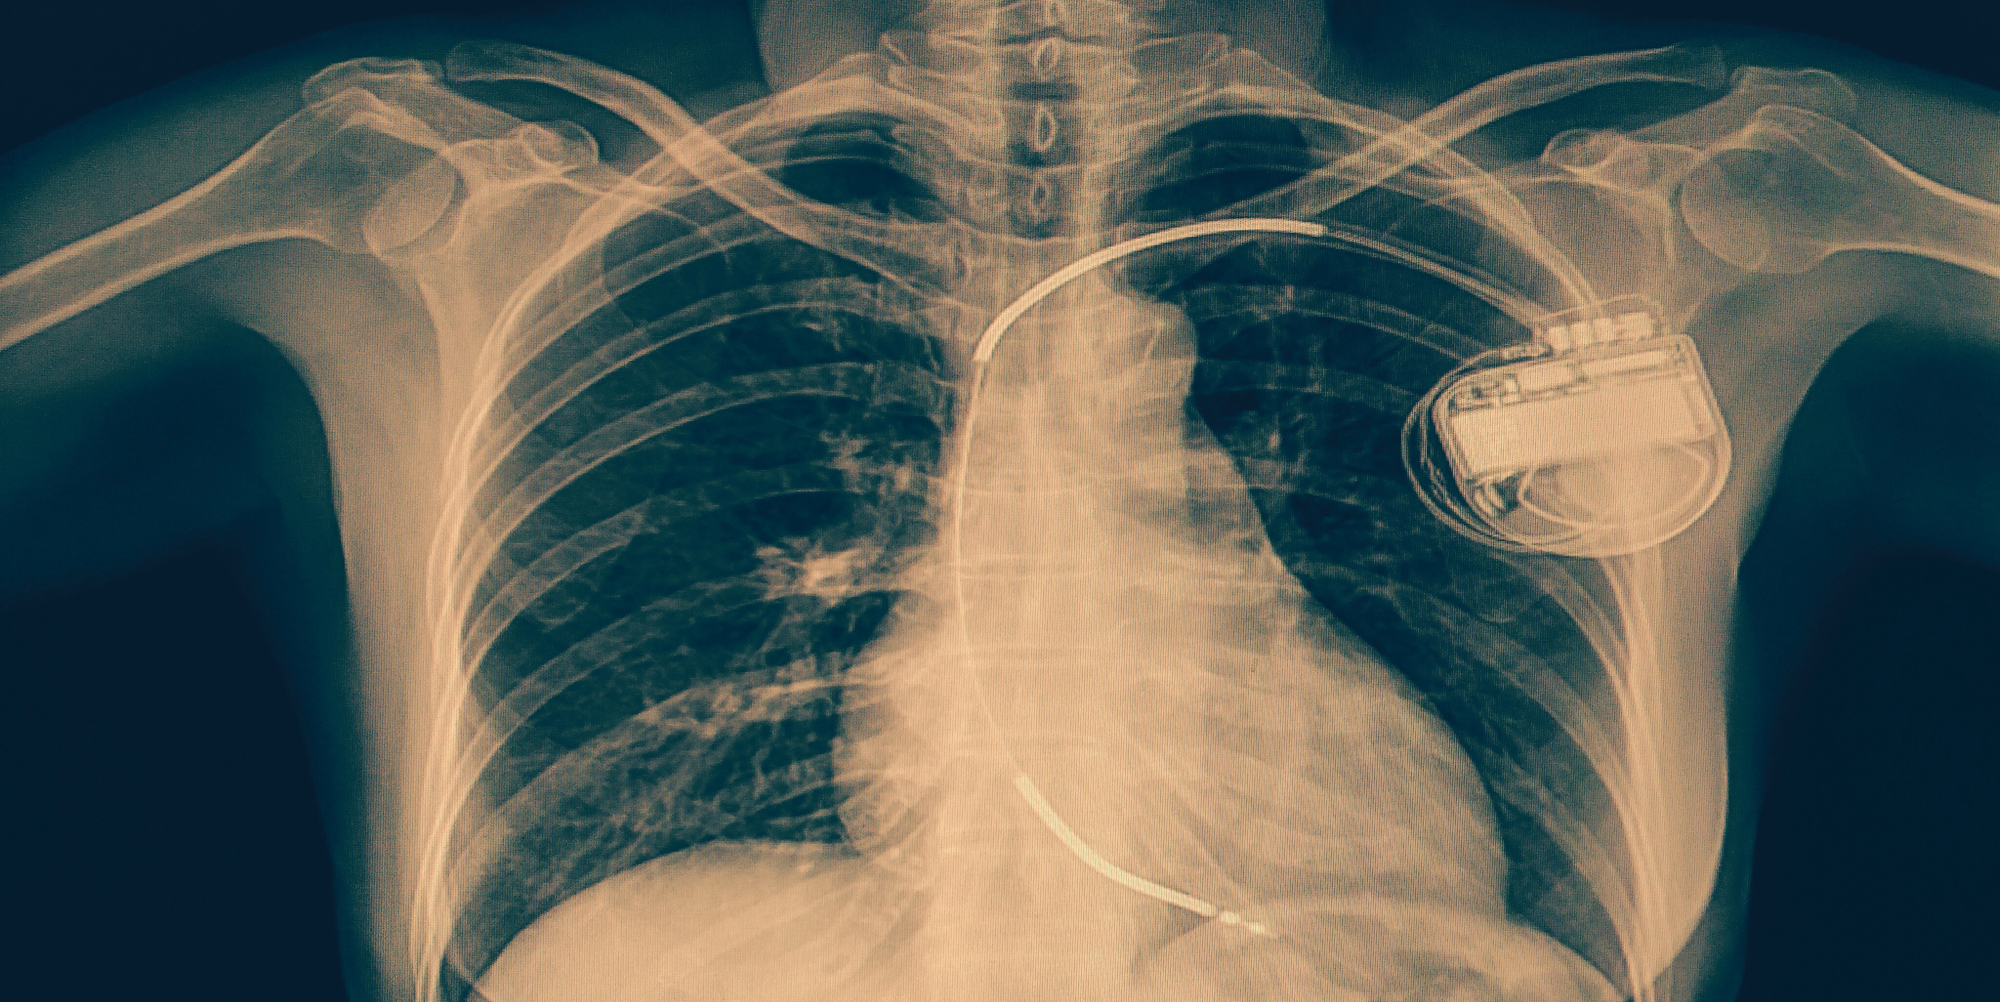

Missed yesterdayās BHRS Devices Webinar or want to watch it again? The full recording is now available in our Members Video Library. We covered essential topics from the BHRS device exam syllabus, including: CXR [...]